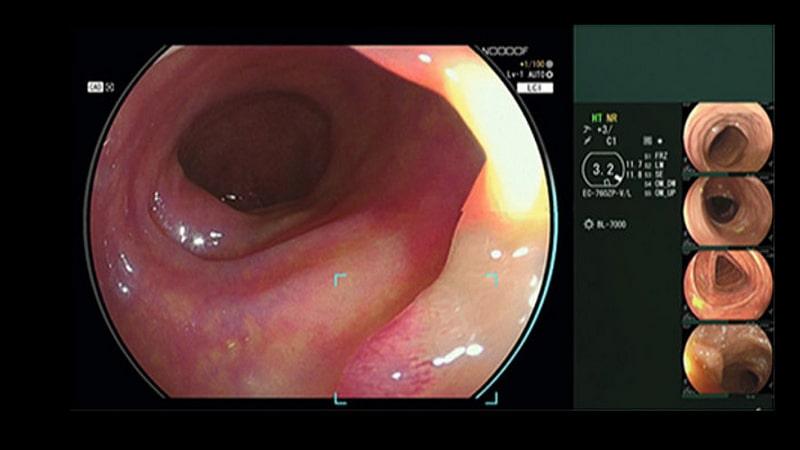

Компания FUJIFILM разработала новую технологию, которая во время колоноскопических исследований способна в режиме реального времени автоматически обнаруживать подозрительные полипы. Технология называется CAD EYE и состоит из аппаратных и программных компонентов, совместимых с эндоскопической системой ELUXEO 7000 этой же компании.

Фирма надеется, что CAD EYE, который автоматически включается в разных режимах визуализации - в режиме белого света (White Light) и в режиме LCI (Linked Colour Imaging), обеспечивает соответствие самым высоким требованиям в отношении яркости и контрастности. Такая технология может помочь повысить точность обнаружения образований (полипов) и уменьшить нагрузку на врачей, выполняющих множество ежедневных процедур.

Для удобства и простоты использования был разработан удобный интерфейс, который не мешает эндоскопическому изображению и сводит к минимуму движение глаз оператора. При обнаружении подозрительного полипа в эндоскопическом изображении блок обнаружения системы указывает область, в которой был обнаружен подозрительный полип, а в непосредственной близости загорается зрительный вспомогательный круг. Кроме того, при обнаружении подозрительного полипа раздается звуковой сигнал.

Эндоскопическая система ELUXEO 7000 применяет принципиально новую технологию 4-LED Multi Light, которая позволяет эндоскопистам использовать самые современные средства эндоскопии с повышенным качеством изображения, обеспечивающие превосходную визуализацию и дифференциацию поверхностей слизистой оболочки и сосудистых структур желудочно-кишечного тракта. Получение точных характеристик обеспечиваются также за счет оптимизированной функции многократного увеличения изображения (Multi Zoom) и рукоятки новой конструкции.